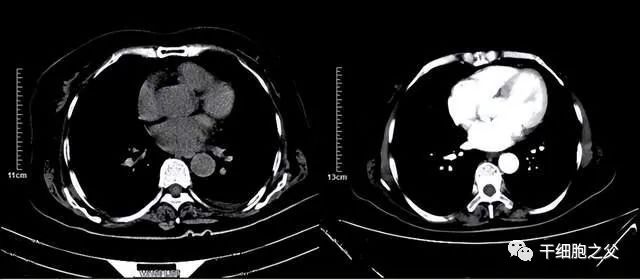

很快孙女士便开始了治疗,细胞免疫治疗过程比她意料中轻松很多,整个过程没有一丝痛苦,治疗后也没有任何不适。仅仅两周的时间,孙女士的身体情况就恢复了许多,能够正常行走,生活自理。CT显示肿瘤明显缩小。

在细胞免疫治疗两个月后孙女士再次进行了4个周期的化疗,期间并没有出现明显副作用。治疗结束后肿瘤标志物明显降低,增强CT显示病症进一步缩小。